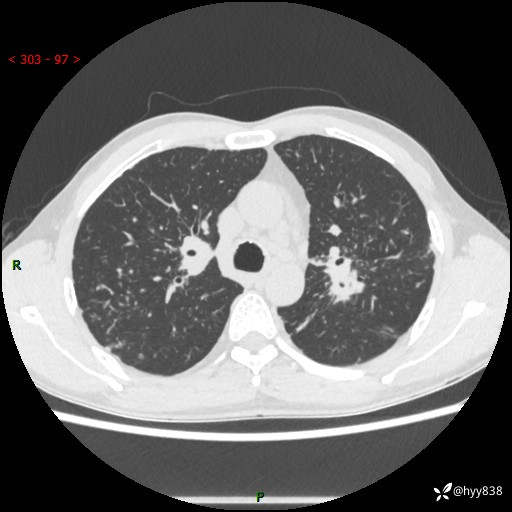

中年男性,咳嗽咳痰1月余。细看:肺、肺门、气管,貌似都有问题---(有结果)

现病史:患者于1个月前受凉后出现间断性咳嗽,伴白色泡沫样痰,无发热寒战、咯血、胸痛胸闷、恶心呕吐、呼吸困难等特殊不适,起初未予特殊处理,后患者就诊当地中医医院,查胸部CT提示支气管炎并双肺感染性病变,经抗感染(哌拉西林舒巴坦),止咳化痰(溴己新、三拗片)等治疗后,患者自诉咳嗽咳痰症状较前缓解,未诉发热等其他特殊不适,近期复查CT提示“肺部感染灶未见消退,双侧肺门增大,双肺散在小结节”,今为求进一步诊治,前来我院就诊,门诊以“肺部感染”收住入院。 患者自起病来精神、食欲、睡眠尚可,大小便正常,体力、体重无明显变化。

胸部CT平扫+增强(两期)